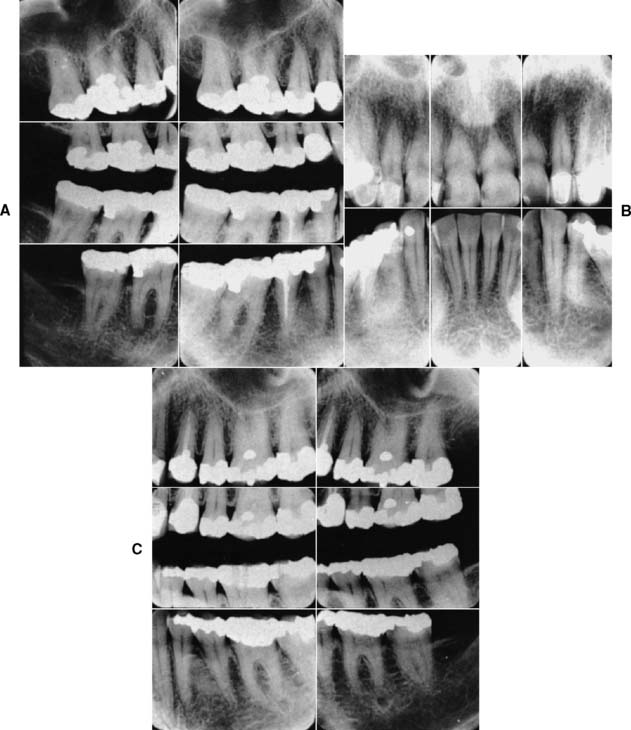

An accurate charting of the state of the dentition reveals important information about the condition of the teeth and facilitates treatment planning. Adequate charting (Fig. 1-19), in addition to all periodontal information, must show the presence or absence of teeth, dental caries, restorations, wear faceting and abrasions, fractures, malformations, and erosions. Missing teeth often have an effect on the position of adjacent teeth (see also the section on arch integrity in Chapter 3). Similarly, the presence of dental caries on one interproximal surface should alert the examiner to carefully inspect the adjacent proximal wall, even if caries is not apparent radiographically. The degree and extent of caries development over time can have a considerable effect on the eventual outcome of fixed prosthodontic treatment. The condition and type of the existing restorations are noted (e.g., amalgam, cast gold, composite resin, all-ceramic). Open contacts and areas where food impaction occurs must also be identified. The presence of wear facets is indicative of sliding contact sustained over time and thus may indicate parafunctional activity (see Chapter 4). Wear facets are often easier to see on diagnostic casts, however (see Chapter 2); during the clinical examination, the location of any observed facet is recorded. Fracture lines in teeth may necessitate fixed prosthodontic intervention, although minor hairline cracks in walls that are not subject to excessive loading can often go untreated and simply be observed at recall appointments (see Chapter 32). The location of fractures should be indicated on the chart, as should any other abnormalities.

Fig. 1-19 A, An appropriate charting system designates the location, type, and extent of existing restorations and the presence of any disease condition, all of which become part of the permanent patient record. B, Radiographic findings obtained from a full-mouth series are correlated with the clinical findings and noted in the record. C to E, Charting is performed to provide a quick reference to conditions in the mouth. The following may be useful: (1) Amalgam restorations (C) are depicted by an outline drawing blocked in solidly to show the size, shape, and location of the restoration. (2) Tooth-colored restorations (D) are depicted by an outline drawing of the size, shape, and location of the restoration. (3) Gold restorations (E) are depicted by an outline drawing inscribed with diagonal lines to show the size, shape, and location of the restoration. (4) Missing teeth are denoted by a large X on the facial, lingual, and occlusal diagrams of each tooth that is not visible clinically or on radiographs. (5) Caries is recorded by circling the tooth number located at the apex of the involved tooth and noting the presence and location of the cavity in the description column corresponding to the tooth number on the right. (6) Defective restorations are recorded by circling the tooth number and noting the defect in the description column.

(Modified from Roberson T, et al: The Art and Science of Operative Dentistry, 4th ed. St. Louis, Mosby, 2002.)

Radiographs provide essential information to supplement the clinical examination. Detailed knowledge of the extent of bone support and the root structure of each standing tooth is essential for establishing a comprehensive fixed prosthodontic treatment plan. Although radiation exposure guidelines recommend limiting the number of radiographs to only those that will result in potential changes in treatment decisions, a full periapical series (Fig. 1-23) is normally required for new patients so that a comprehensive fixed prosthodontic treatment plan can be developed. Patient exposure can be minimized by using a technique that provides the most information with a minimal need for repeat films and by using appropriate protection. The use of digital radiography can further help reduce radiation exposure.

Fig. 1-23 A to C, A full-mouth radiographic survey should enable the dentist to make a detailed assessment of the structure of each tooth and its bone support.